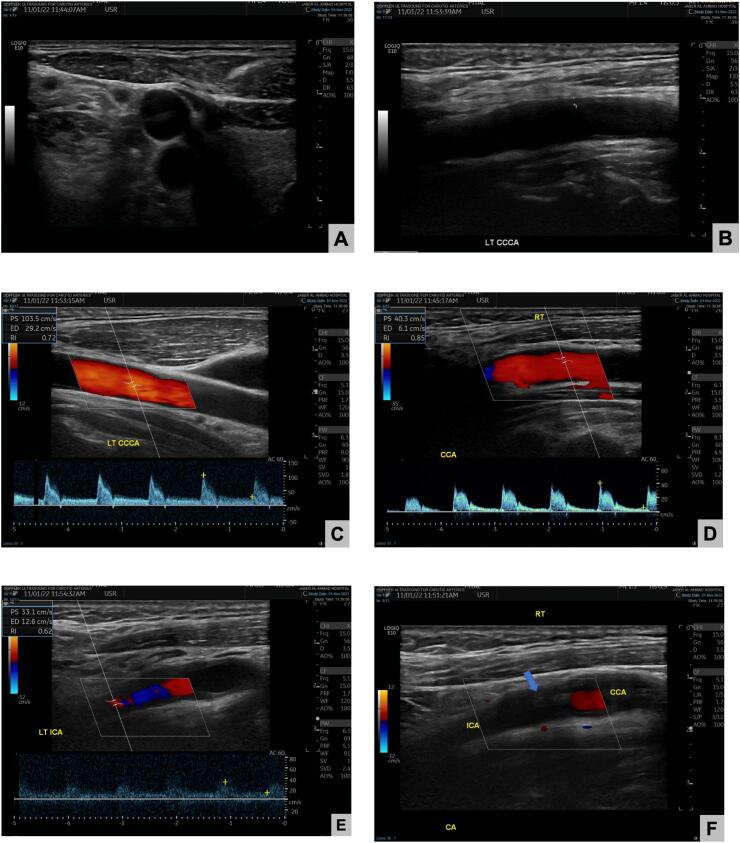

Anticoagulation started by the vascular team and further investigations were obtained such as carotid doppler for extracranial carotid system which showed (Fig. 2):

Fig. 2.

Carotid doppler scanning:

A: Patent common carotid artery

B: Patent left common carotid artery

C: Normal left common carotid artery with normal waveforms and anterograde flow

D: Retrograde flow of the right common carotid artery according to the carotid doppler.

E: Average velocity along the carotid arteries and no areas of abnormal high velocity

F: ICA Stump in the right ICA.